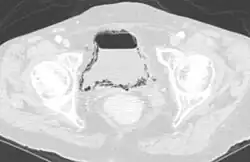

La principale cause de pneumaturie est la présence d’une fistule uro-digestive (souvent retrouvée lors d'une diverticulite du sigmoïde).